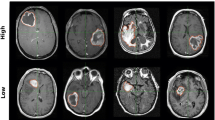

Figure 2 shows an example of a hybrid front subject from our autopsy dataset with corresponding autopsy pathology, confirming that areas of predicted hypercellular and hypocellular front correspond to their expected pathological features on histological tissue samples. Areas of hypercellular front show increased nuclear density on histology, areas of hypocellular front show reduced nuclear density and increased ECF presence, and both fronts are readily distinguishable from normal appearing tissue from beyond the tumor front. Figure 3 shows examples of each tumor phenotype, along with their respective Kaplan-Meier survival curves. Well-circumscribed patients showed trending-to-longer survival times compared to other phenotypes (hypocellular front: HR = 2.02, p = 0.03; hypercellular front: HR = 2.0, p = 0.06; hybrid front: HR = 1.75, p = 0.09), with hypocellular front tumors showing the shortest overall survival times. Kaplan Meier curves for patients who have and have not received bevacizumab therapy, split by phenotype, are presented in Fig. 4. No survival benefit was seen for bevacizumab therapy within the hypercellular front group (HR = 1.16, p = 0.77) or well-circumscribed group (HR = 1.81, p = 0.15). Survival benefit was however observed for both the hypocellular front group (HR = 2.35, p = 0.024) and the hybrid front group (HR = 2.45, p = 0.032), both phenotypes containing hypocellular presence.

(left) Examples of each phenotype observed in the presurgical dataset. (right) Kaplan-Meier curves for overall survival within each phenotype. Well-circumscribed patients showed trending-to-significant longer overall survival than hypercellular (HR = 2.0, p = 0.06), hypocellular, (HR = 2.02, p = 0.03), and hybrid (HR = 1.75, p = 0.09) phenotypes